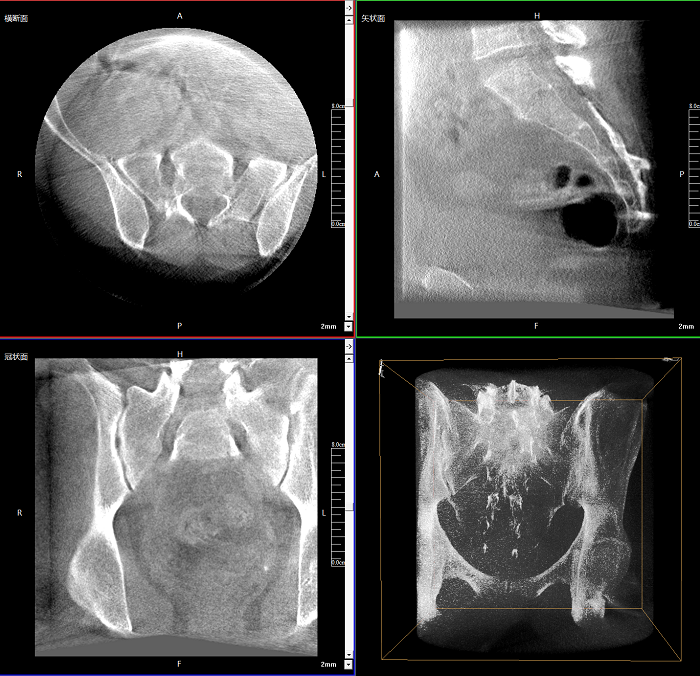

術(shù)中實(shí)時(shí)生成橫斷面、矢狀面、冠狀面及三維影像,可在任意切面、任意角度評估植入物和解剖結(jié)構(gòu)的相對位置。

術(shù)中CT檢查 減少翻修概率

通過術(shù)中三維影像的檢查,可以立即發(fā)現(xiàn)植入物的錯(cuò)位,減少不必要的第二次手術(shù),減少并發(fā)癥概率以及感染風(fēng)險(xiǎn)。

Clinical picture

臨床圖片